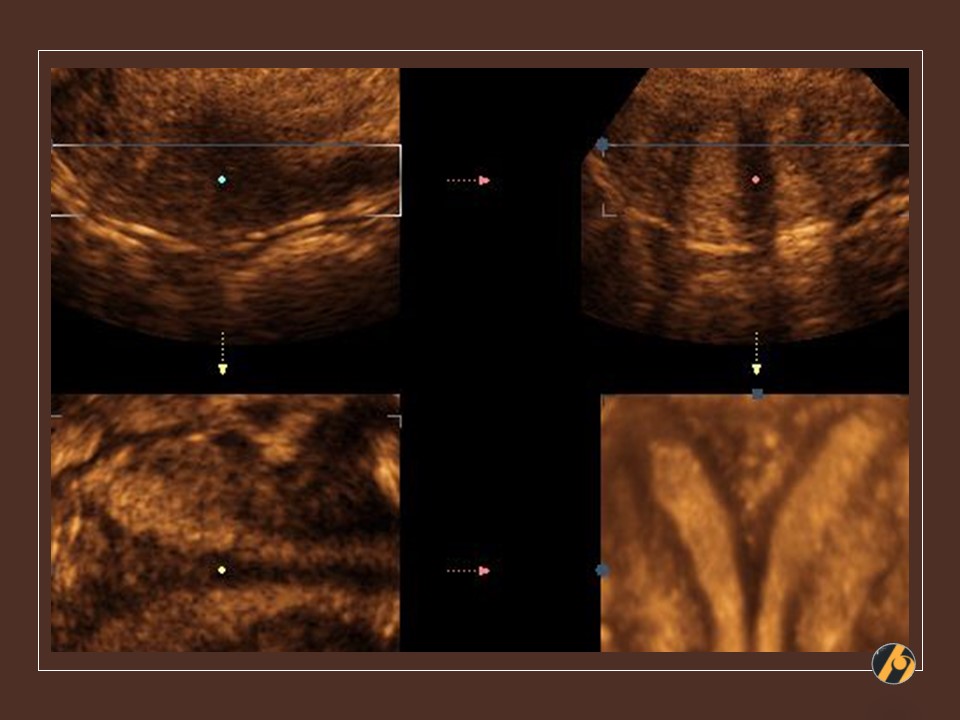

3D ultrazvuk / frontalna ravnina

3D ultrazvučna rekonstrukcija maternične šupljine pokazuje ravan fundus i manji oštri septum u gornjoj trećini kavuma.